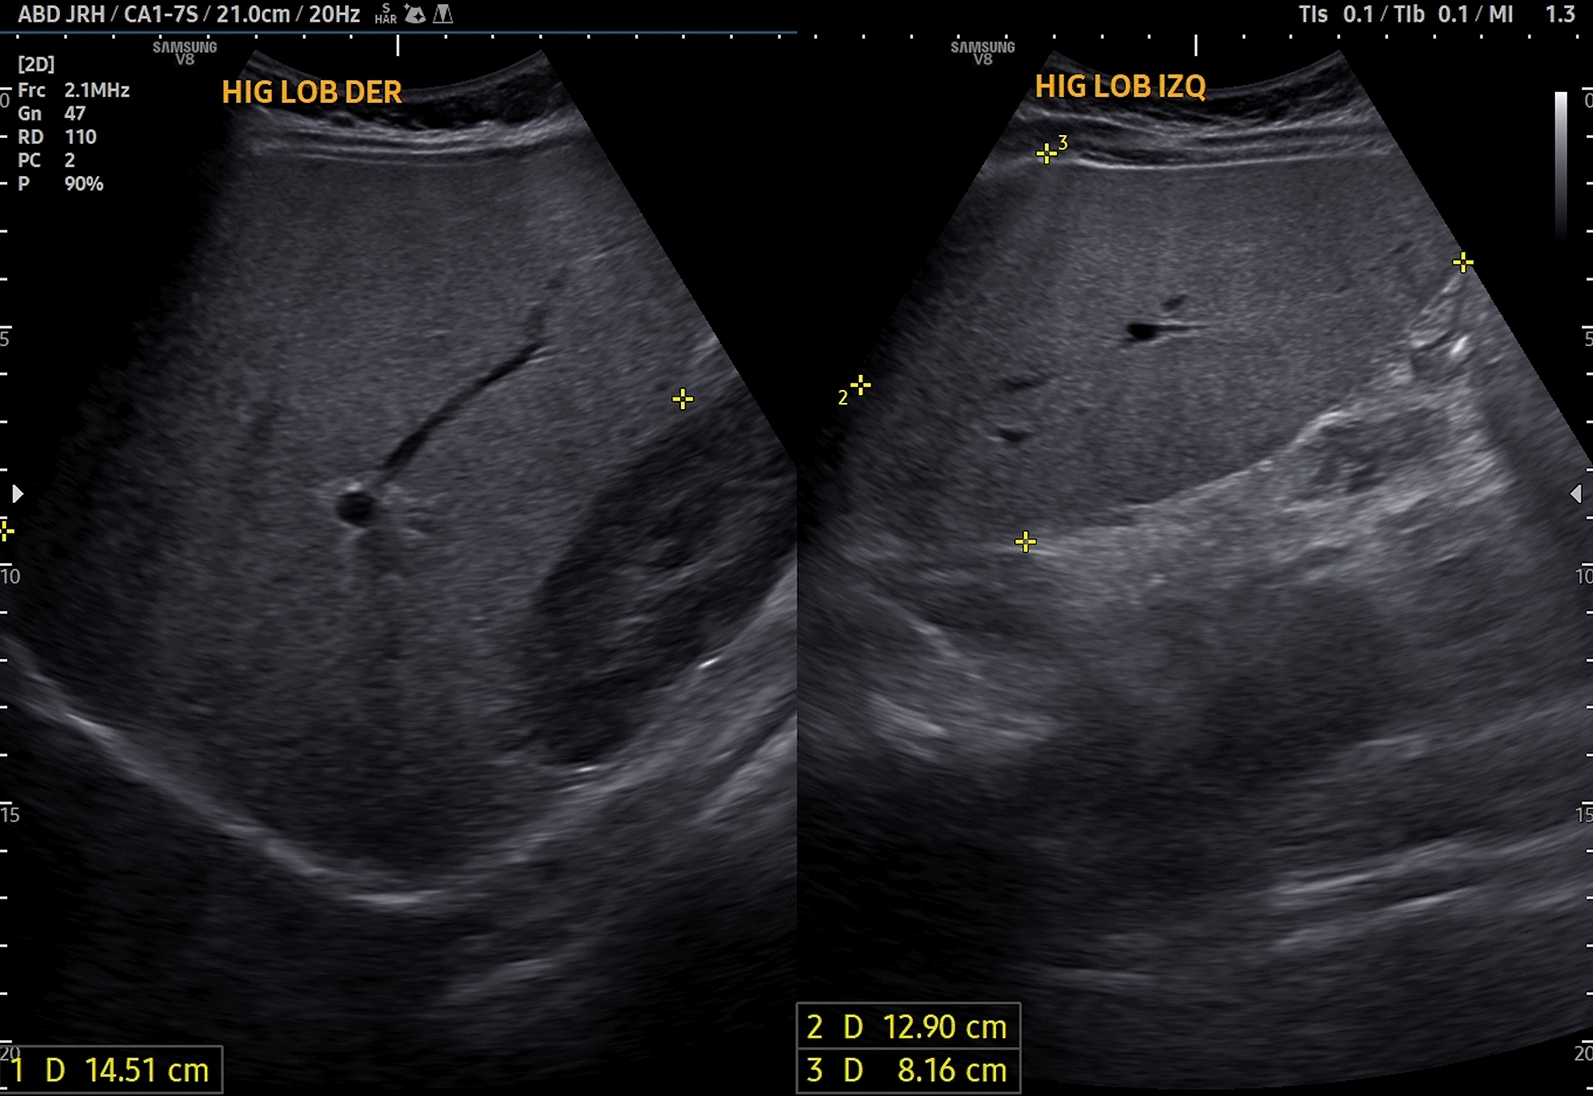

Case presentation: We report a 16-year-old Honduran mestiza female patient with CSPP1-related Joubert syndrome who presented with insulin resistance, early onset diabetes, dyslipidemia, and metabolic dysfunction-associated steatotic liver disease. Notably, she lacked the typical neurological symptoms of Joubert syndrome. Brain magnetic resonance imaging revealed cerebellar vermis hypoplasia, confirming the diagnosis. Genetic testing identified a pathogenic heterozygous CSPP1 variant (c.3052C > T, p.Gln1018), supporting the diagnosis of CSPP1-related Joubert syndrome.